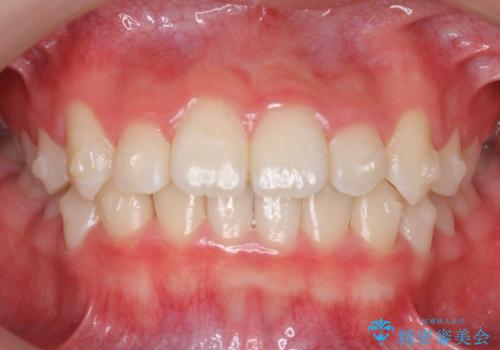

八重歯 歯を抜かずにインビザラインで

- 八重歯を主訴に来院。

抜かずに歯を少し削って入れる方法で並べました。

10代のうちに矯正をしておくと歯の移動は簡単で、歯ぐきも下がりにくいです。